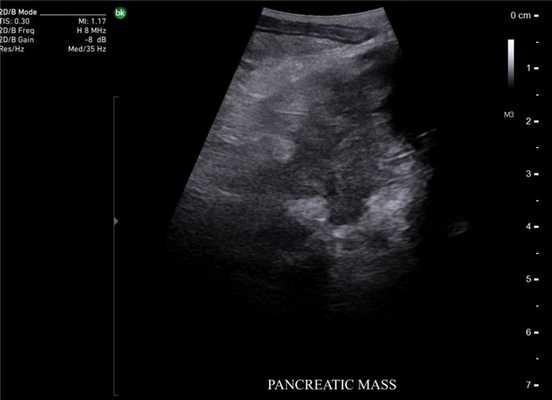

В панкреатологии ИОУЗИ применяют как при доброкачественных процессах, например, при хронических панкреатитах для локализации главного панкреатического протока, выявления вирсунголитиаза, поиска псевдокист в паренхиме поджелудочной железы и стенке двенадцатиперстной кишки, недоступных визуальному осмотру, так и при злокачественном поражении. Наиболее сложным является оценка измененной ткани головки поджелудочной железы с целью дифференциальной диагностики псевдотуморозного панкреатита и рака.

При злокачественных поражениях поджелудочной железы по данным ИОУЗИ проводят окончательную оценку резектабельности и операбельности образований [22]. Взаимоотношение опухоли с окружающими сосудистыми структурами выполняют в продольной и поперечной плоскости сканирования относительно оси сосуда. В первом случае оценивают протяженность контакта и измеряют спектральные характеристики кровотока, во втором - проходимость просвета сосуда и площадь контакта образования с окружностью. По последнему критерию разделяют резектабельные опухоли, когда площадь контакта составляет менее 25% (90º) окружности, условно-резектабельные - опухоль охватывает 25-75% (90º-270º) окружности, нерезектабельные циркулярное вовлечение сосуда более 75% (270º) окружности [23].

ИОУЗИ нейроэндокринных опухолей поджелудочной железы после пальпации является «золотым стандартом» в хирургии данного вида образований [24]. Если при ультразвуковом исследовании не удается четко выявить наличие гипоэхогенной гиперваскулярной опухоли с четкими контурами, которая интенсивно копит контраст в раннюю артериальную фазу, то можно высказать предположение о наличии незидиобластоза [25].